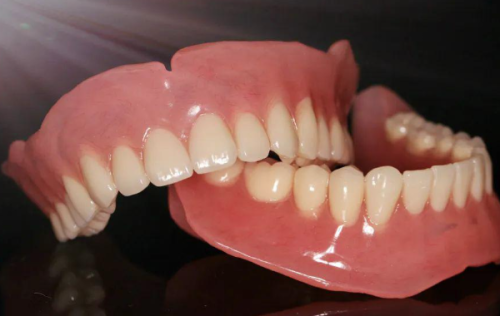

在南宁蓝天口腔,单颗瑞士士卓曼ITI种植牙以其极高的性价比脱颖而出。通常情况下,瑞士iti种植牙的市场价格相对较高,比如广宁蓝天口腔种植牙收费价目表显示,瑞士iti种植牙价格为13600元起/颗。而南宁蓝天口腔推出的限时活动价,单颗瑞士士卓曼ITI种植牙只需5980元起。这个价格包含了瑞士原装ITI种植体、基台、全瓷冠,还含数字化导板设计费。可以说,用如此实惠的价格就能享受到高品质的种植牙服务,在口腔医疗市场中是非常难得的。这对于那些想要进行种植牙修复,但又担心费用过高的患者来说,无疑是一个突出的机会。

其次,在技术特点方面,瑞士士卓曼ITI种植体本身具有出色的品质。它采用了独特的表面处理技术,能够促进种植体与牙槽骨之间的骨结合,使种植体更加稳固地扎根在口腔内。而且,这种种植体具有良好的生物相容性,能够减少人体对种植体的排异反应,降低感染的风险。同时,全瓷冠的使用不仅美观自然,而且具有良好的耐磨性和咀嚼性能,能够满足患者正常的饮食需求。